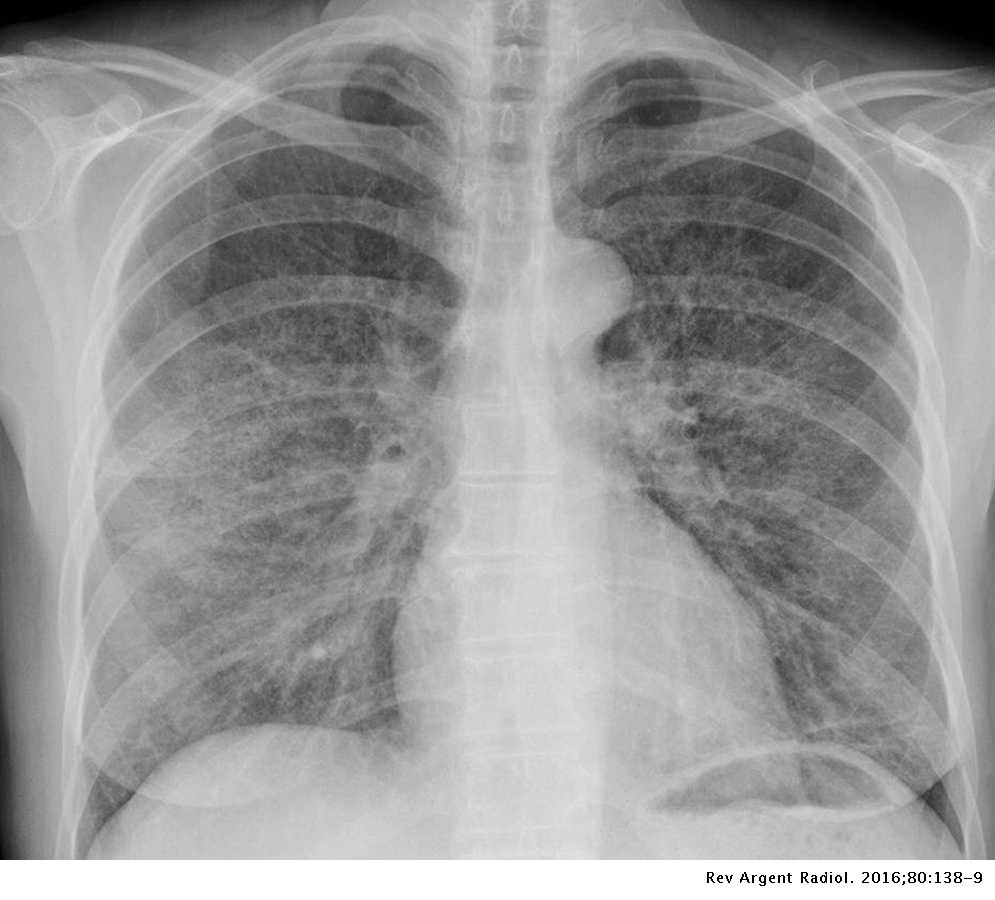

- Bronconeumonía multifocal o neumonía lobulillar

- La bronconeumonía (neumonía lobulillar) se caracteriza histológicamente por una inflamación predominantemente peribronquiolar. Aunque inicialmente irregular, la progresión de la enfermedad da como resultado una consolidación lobulillar y segmentaria. La inflamación peribronquiolar inicial se manifiesta radiológicamente como nódulos parcheados en el espacio aéreo con márgenes mal definidos. Un broncograma aéreo generalmente está ausente. Los organismos causantes más comunes de bronconeumonía son S. aureus, H. influenzae, P. aeruginosa y bacterias anaerobias.